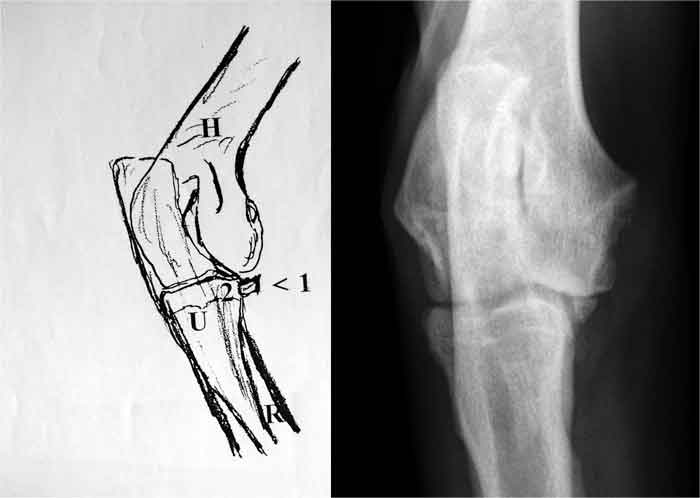

| Abb. 5 Fila Brasiliero, 6 Monate. Linkes Ellbogengelenk, seitlicher Strahlengang. IPA. Weit dislozierter isolierter Processus anconaeus (1). Die Incisura trochlearis (2)ist deformiert und zeigt deutliche Knochenverdichtungen. Bei 3 deutliche Stufenbildung zwischen dem Radiuskopf und der Gelenkfläche der zu kurzen Ulna. |

![]() |

| Abb. 8 DSH, 6 Monate Rechtes Ellbogengelenk, seitlicher Strahlengang, gebeugtes Gelenk. IPA. Nicht dislozierter isolierter Processus anconaeus (1).Eine Stufenbildung zwischen Radius und Ulna ist nicht erkennbar. Humerus (H), Radius (R) Ulna (U) |